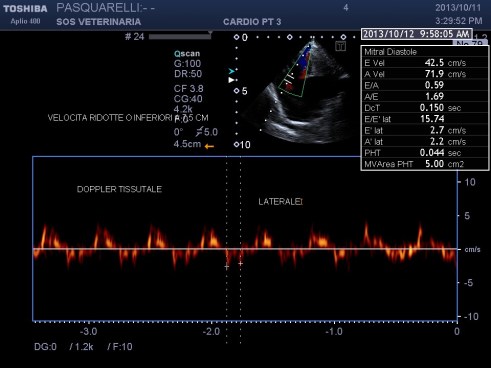

Per avere una idea del grado di pericolosita’ della malattia basta visionare lo smoke (effetto fumo) nell’atrio sx del soggetto e il voluminoso trombo fluttuante e martellante i lembi valvolari .

Una diagnosi precoce e una corretta terapia antiaggregante avrebbe consentito a questo soggetto di vivere tranquillamente fino allo scompenso congestizio diastolico inevitabile con l’aumentare del grado di ipertrofia.

Il soggetto aveva solo due anni di eta’ e aveva eseguito il test genico risultato negativo , da qui l’importanza, per una corretta analisi cardiologica ,dell’ecocardiogramma ,mai eseguito in questo caso .